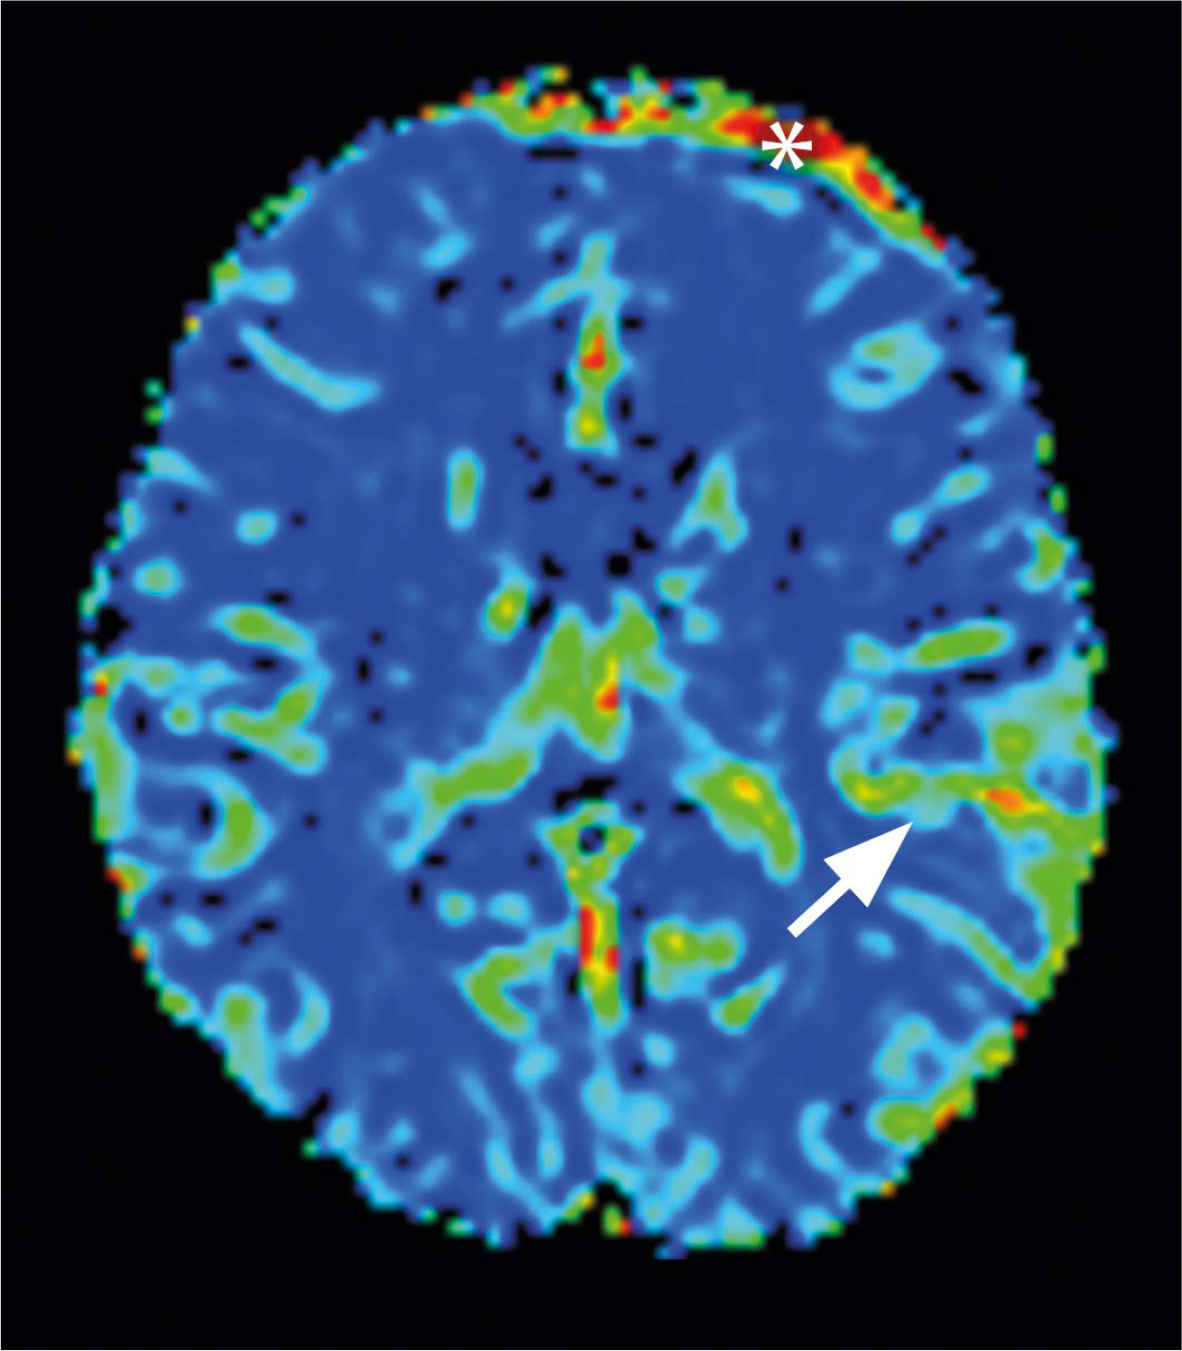

MRI perfusion parameters after index seizures (grey matter)

| N | M | Me | SD | ||

|---|---|---|---|---|---|

| N | BF | 25 | 101,7 | 93 | 40,8 |

| N | BV | 25 | 8 | 7 | 3,9 |

| N | MTT | 25 | 6,9 | 6,9 | 2,9 |

| N | TTP | 25 | 13,9 | 13,8 | 2,3 |

| P | BF | 5 | 265,85 statistically significant difference (p < 0,001) | 234 | 56,3 |

| P | BV | 5 | 25,5 statistically significant difference (p < 0,001) | 27,6 | 4,7 |

| P | MTT | 5 | 5,7 | 5 | 1,2 |

| P | TTP | 5 | 14,5 | 13,5 | 4,5 |